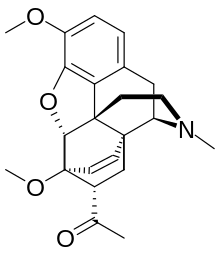

Oripavine derivatives

Thienorphine

- 7-PET

- Acetorphine

- Alletorphine (N-allyl-noretorphine)

- BU-48

- Buprenorphine

- Buprenorphine-3-glucuronide

- Cyprenorphine

- Dihydroetorphine

- Etorphine

- Homprenorphine

- 18,19-Dehydrobuprenorphine (HS-599)

- N-cyclopropylmethylnoretorphine

- Nepenthone

- Norbuprenorphine

- Norbuprenorphine-3-glucuronide

- Thevinone

- Thienorphine

Structures

| Oripavine derivatives | ||||

7-PET 7-PET |

Acetorphine Acetorphine |

Alletorphine Alletorphine |

BU-48 BU-48 |

Buprenorphine Buprenorphine |

Cyprenorphine Cyprenorphine |

Dihydroetorphine Dihydroetorphine |

Etorphine Etorphine |

Homprenorphine Homprenorphine |

18,19-Dehydrobuprenorphine 18,19-Dehydrobuprenorphine |

N-cyclopropylmethylnoretorphine N-cyclopropylmethylnoretorphine |

Nepenthone Nepenthone |

Norbuprenorphine Norbuprenorphine |

Thevinone Thevinone |

Thienorphine Thienorphine |